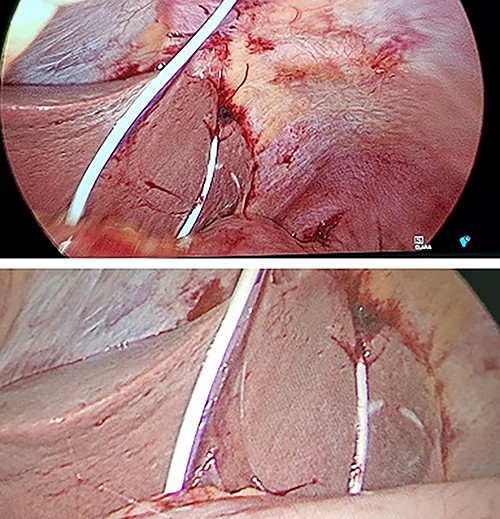

A diagnostic laparoscopy was undertaken to identify any intra-abdominal injuries and safe removal of drain. Laparoscopy findings confirmed an intraperitoneal course with a laceration in segment III of the liver and penetration of diaphragm (Fig. 2). There was clotted blood in the pelvis, which was likely due to liver injury. There was no evidence of viscus perforation identified to explain the pneumoperitoneum. More likely this air had entered during the initial procedure although a small viscus perforation that had already sealed would be a possibility. The pericardial drain was removed, and haemostasis confirmed. The patient was observed in the intensive care unit and made a full recovery.

Intraoperative photographs during laparoscopy for removal of intraperitoneal pericardial drain.